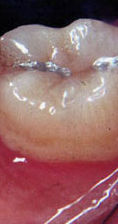

pase el ratón sobre las piezas para ver: bolsa, recesión y movilidad